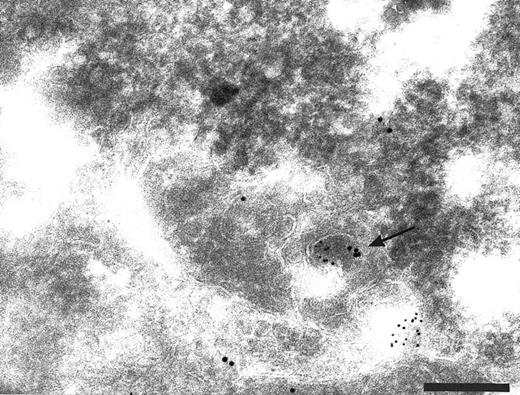

Finally, to show the presence of TFPI in early endosomes, a compartment which has the ability to recycle back to the plasma membrane, the TFPI was colocalized with antibodies to the human transferrin receptor (HTfR). Using both polyclonal and monoclonal antibodies to the human TfR we have shown a colocalization with TFPI in membranous organelles on sections of endothelial cells (Fig 5 and Table 1). This demostrated the possibility that TFPI could be recycled back to the cell surface.

Cryosections of HUVEC labeled with antibodies to human transferrin receptor (HTfR, small gold) and anti-TFPI (large gold). Transferrin receptor recycles from the cell surface via early endosomes. Small vesicles (arrows) label with anti-HTfR and anti-TFPI. Bar = 0.2 μm.